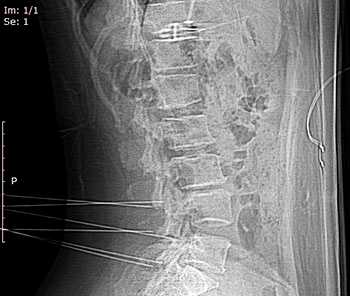

КТ поясничного отдела позвоночника. Деформирующий спондилоартроз. Умеренно выраженные дегенеративные изменения дугоотростчатых суставов

Лечение заболевания направлено на ликвидацию болевого синдрома, оптимизацию нагрузки на позвоночник и предотвращение дальнейшего прогрессирования болезни. При сильных болях назначают НПВП, при выраженных мышечных спазмах - миорелаксанты центрального действия. Используют местные противовоспалительные средства (мази, крема, гели). При упорном болевом синдроме проводят блокады фасетчатых суставов смесью анестетиков (новокаина или лидокаина) и глюкокортикоидных препаратов. Процедура осуществляется под контролем аппарата для КТ-флюороскопии или рентгенографии. Помимо лекарственных средств для устранения болевого синдрома при спондилоартрозе применяют фонофорез с гидрокортизоном, ионогальванизацию с лидокаином или новокаином, модулированные токи и магнитотерапию.